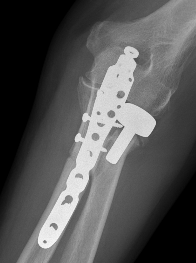

Olecranon plate + ORIF Type II coronoid process + radial head replacement

Olecranon plate with radial head replacement

Olecranon plate with radial head replacement + LCL repair

Olecranon plate + medial coronoid buttress plate + radial head replacement